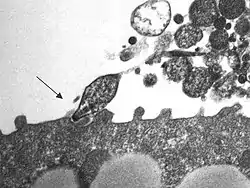

M. pneumoniae es un patógeno extracelular que se adhiere al epitelio respiratorio mediante una estructura de anclaje especializada, que se forma en un extremo de la célula. Esta estructura está constituida por un complejo de proteínas para adherencia, en la que destaca la adhesina P1 como la más importante. Las adhesinas interactúan de manera específica con los receptores de glucoproteínas sialidadas en la base de los cilios de la superficie de las células epiteliales (así como en la superficie de los eritrocitos). A continuación tiene lugar la ciliostasis, tras la que son destruidos en primer lugar los cilios y posteriormente las células del epitelio ciliar. La pérdida de estas células interfiere en el aclaramiento normal de las vías respiratorias superiores y permite que las vías respiratorias inferiores se contaminen con microorganismos y sufran una irritación mecánica. Este proceso es el responsable de la tos persistente que tienen los pacientes con enfermedad sintomática.